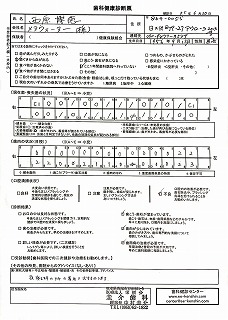

092 病院定期検査

2024-0210西原クリニック検査結果